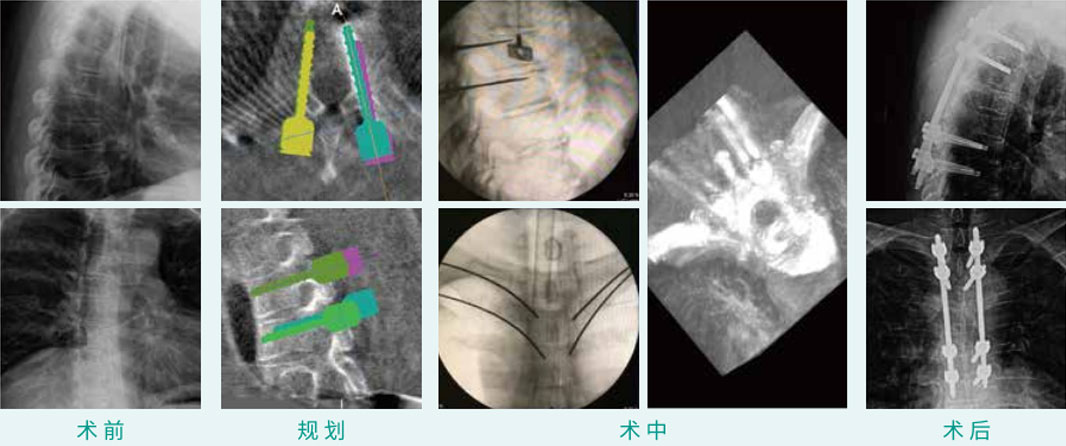

天玑? 辅助T2, T3, T6, T7椎弓根钉经皮内牢靠术

基本情形:患者男,55岁

机械人累积用时:20分钟

植入物:8枚经皮椎弓根螺钉

病例泉源:中国医科大学隶属第一医院 朱悦 丛琳